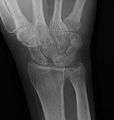

Scapholunate disassociation